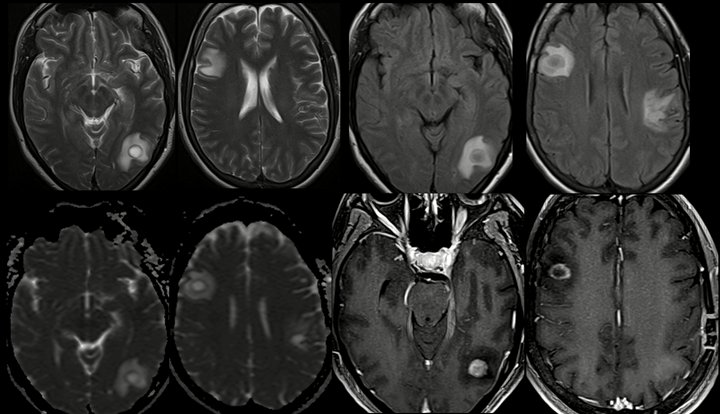

En el enfoque del paciente con síndrome súbito de alteración del lenguaje dado por afasia de conducción, se descarta síndrome neurovascular agudo en estudio imagenológico (ver figura 1), con hallazgo de lesión tipo masa frontoparietal izquierda con edema vasogénico que capta medio de contraste paramagnético en su periferia. En estudios de extensión con líquido cefalorraquídeo normal, film array negativo, gene xpert ultra TB negativo, ADA 2.17, HIV negativo y perfil autoinmunidad normal.

Se indican estudios de compromiso tumoral con reporte de biopsia guiada por estereotaxia que reporta tejido cerebral con severos infiltrados de histiocitos espumosos, negativo para tumor y vasculopatía. Se considero sospecha de enfermedad desmielinizante, con resonancia de neuroeje normal, se inicia pulsos de metilprednisolona por 5 días con mejoría clínica y se da egreso con reportes pendientes de bandas oligoclonales, anti-NMO y anti-MOG. Posteriormente a los 20 días del inicio del cuadro clínico, consulta por múltiples episodios de crisis focales sin alteración del estado de conciencia motor de inicio clónias en cara con postura tónica en flexión en miembro superior derecho. A la exploración neurológica con alteración de la sensibilidad en miembro superior derecho de todas las modalidades sensitivas. Se realiza neuroimagen control (ver figura 2), con videoEEG normal y reporte de bandas oligoclonales tipo II, anti-NMO y anti MOG negativo. Se considera cuadro sugestivo de esclerosis múltiple tumefacta y se inicia tratamiento con Rituximab dado recurrencia 1 y Carbamazepina para la epilepsia focal estructural.